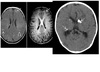

Low flow vascular malformation without intervening normal brain tissue ?

Cavernous malformation **Popcorn ball appearance with complete peripheral hypointense hemosiderin rim on T2 MR** gradient echo. Nb - Normal intervening brain tissue that developed compilation from radiation therapy = Capillary telangiectasia